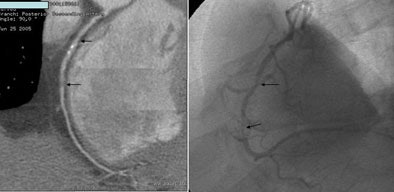

![]() |

| A 59-year-old man presented with classic chest pain symptoms to the ER five days earlier. He was asymptomatic upon presentation to the practice, but opted for an office-based CTA rather than wait three weeks to see a cardiologist. Images top to bottom: Right coronary artery stenosis (arrows) shown on 64-slice CTA at left, cardiac catheterization at right. Next, a normal left circumflex artery (arrows) is depicted on 64-slice CTA at left, cardiac catheterization at right. Next two image sets: Left anterior descending artery stenosis (arrows) is seen on 64-slice CTA at left, cardiac catheterization at right. Bottom image shows excellent outcome on cardiac cath following stenting. |